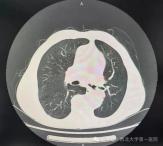

西北大学第一医院支气管镜“多技术联用” 攻克复杂大气道疾病难题

日前,西北大学第一医院呼吸与危重症医学科成功完成首例支气管镜下高频电刀治疗 + 冻切冻融治疗 + 氩气刀治疗的复杂介入手术,为一名病情危重的患者精准切除肿瘤组织、开通阻塞气道并明确...